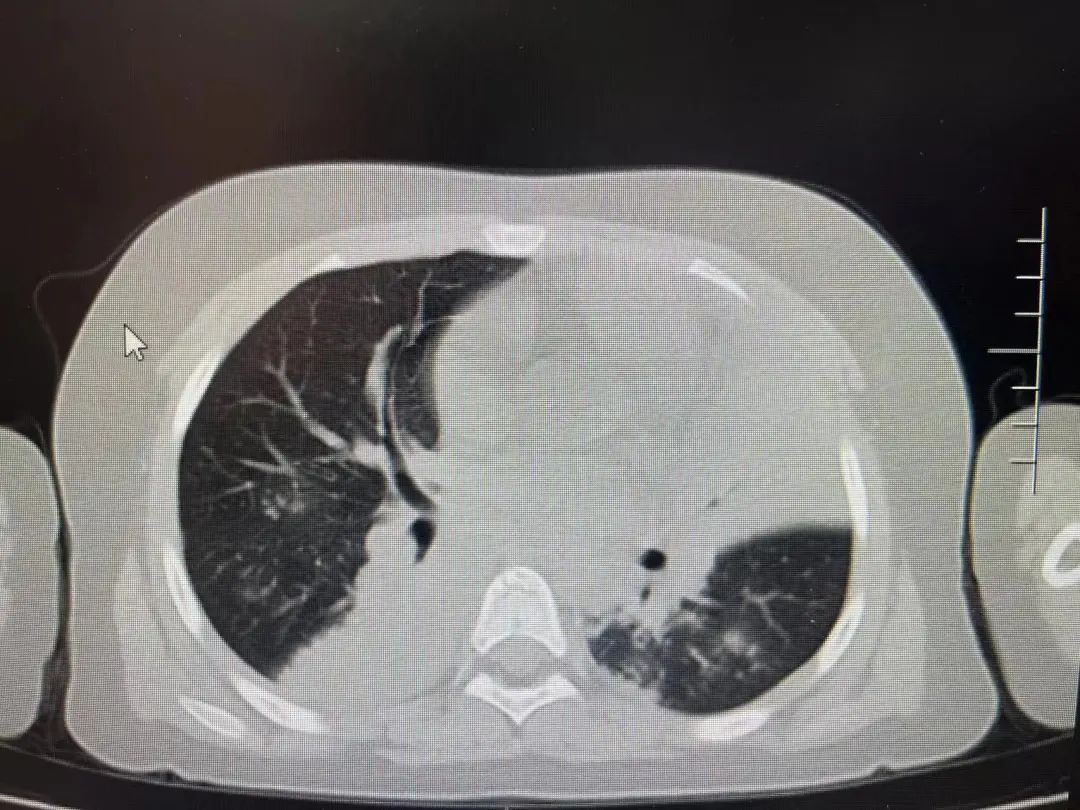

经胸部CT检查,发现患儿双肺都出现了肺不张的情况,超过2/3肺叶实变,再综合血检结果,诊断为重症支原体肺炎,遂住院治疗。在PICU治疗期间,又对症进行了支气管镜灌洗治疗,效果明显。